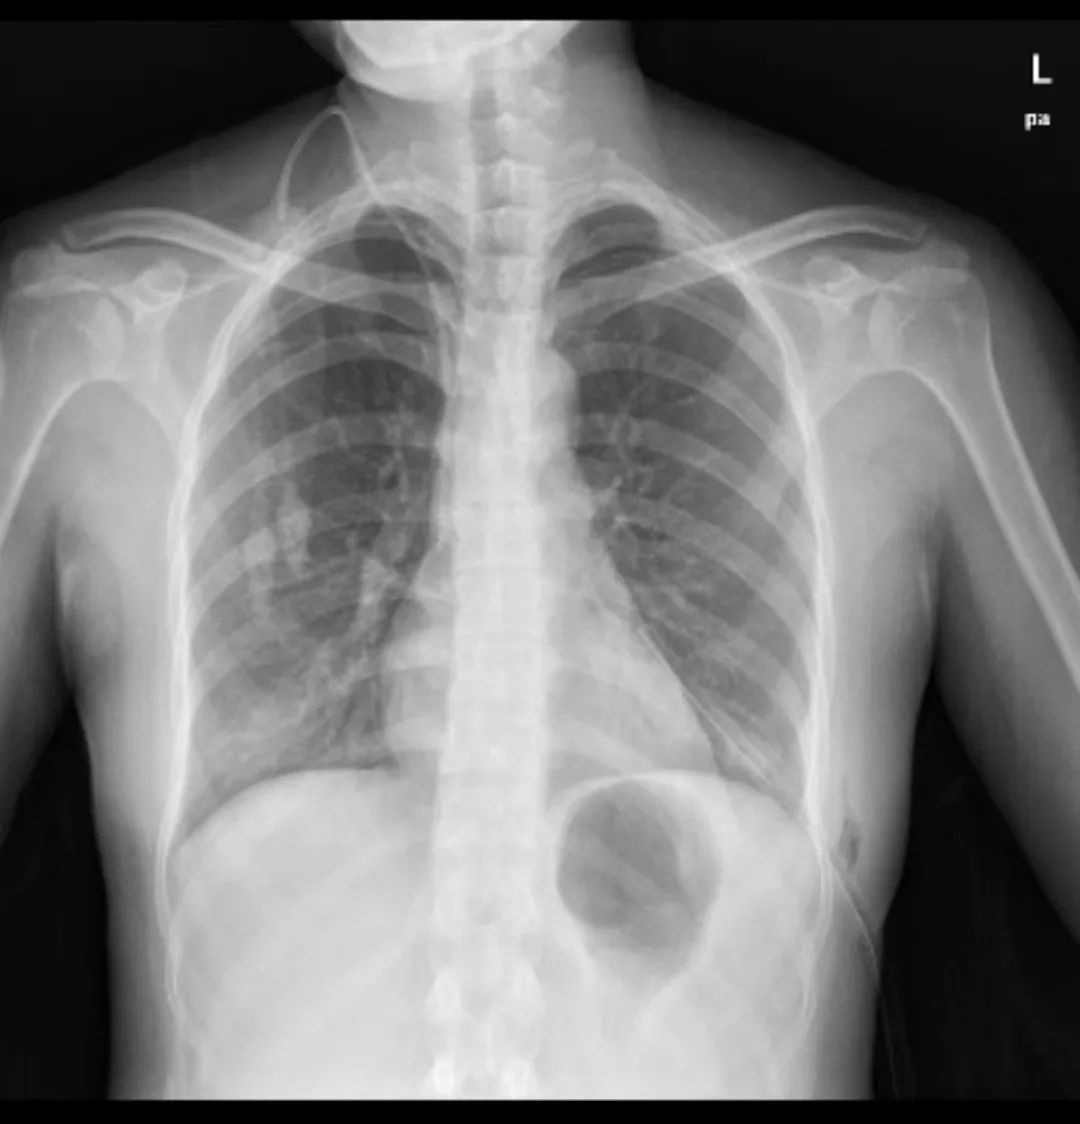

近日,杨女士从约3米高的楼梯摔下,倒地时还将厕所的玻璃门撞碎,导致腿和身上多处被扎伤。在附近医院处理伤口后,杨女士感觉肚子也十分疼痛。医生为其拍摄腹部X线片,发现她的部分脏器冲入左侧胸腔,形成严重膈疝,病情超出当地医院的救治能力。

整个胃进入左胸腔,将左侧肺压缩,并挤走了心脏

病情已不容再拖延了,杨女士被转诊到中山大学附属第一医院急诊科。此时她的呼吸因左肺遭挤压而变得非常困难,整个人无法平卧。万幸的是,尽管脏器移位,但杨女士的腹腔并未出血,胃部也没有穿孔,否则她就会在2小时至4小时内休克乃至死亡。但时间拖得越久,杨女士胃坏死的可能性也越来越高。

术后患者复查胸片,腹腔器官都已“回家”

术后5天,杨女士复查胸部X线片,发现原来进入左侧胸腔的各器官已经归位,被压缩的左侧肺部基本恢复正常模样,膈疝也已消失。术后第6天,杨女士顺利出院。